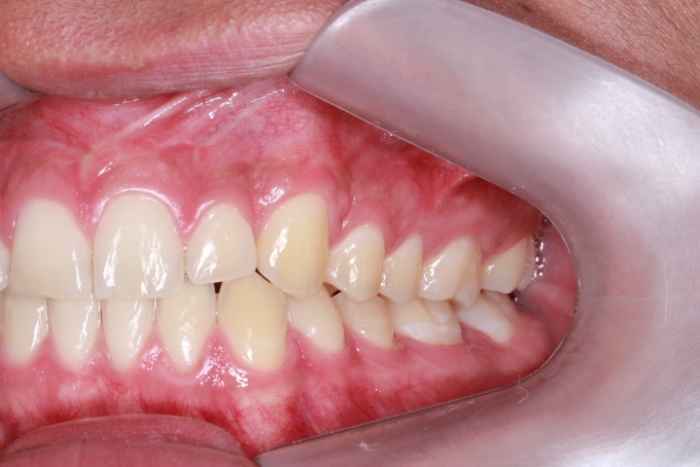

com tratamento ortodôntico finalizado  - Clínica Cliniface

com tratamento ortodôntico finalizado